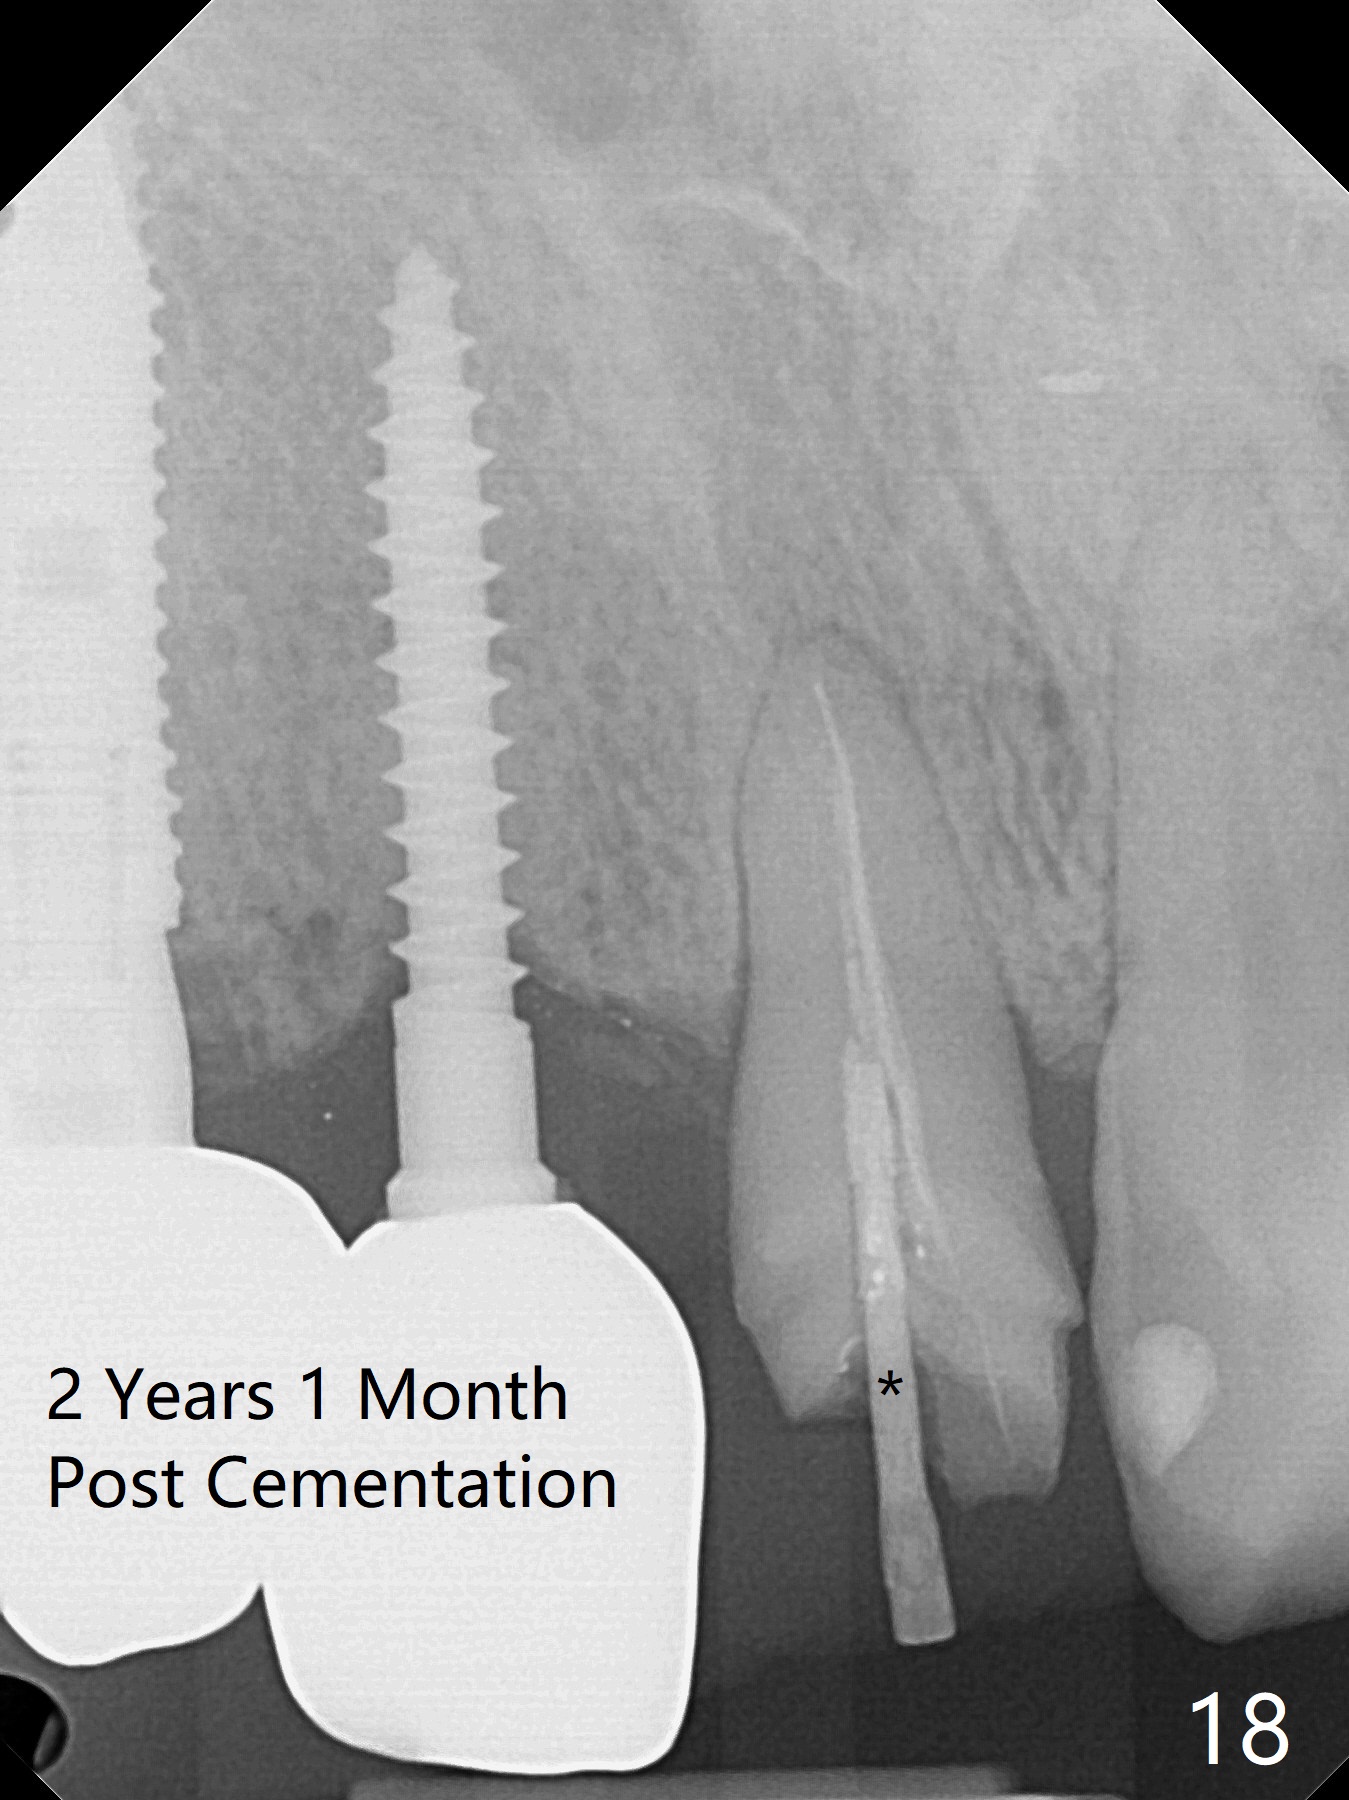

Since the ridge at #7 is ~ 4 mm, a 2.5x14 mm 1-piece implant is placed (Fig.8) after 1.2 mm (Fig.7), and 1.5 mm drills at 12 mm and 2 mm drill at 8 mm. Later the implant is placed deeper (Fig.10). There is no bone loss 7 or 12 months postop, respectively (Fig.11,12). After Diode gingivectomy, there is papillary formation (Fig.13). No provisional is provided after impression (with the abutment torqued at #6) for oral hygiene. With access holes at #6 and 7, crowns are bonded with minimal residual cement (Fig.14 <, which is removed later). There is no hard (Fig.15,16) or soft (Fig.17 *) atrophy 26 months postop, i.e., 13 months post cementation, due to the presence of socket shield (Fig.15 <, as compared to Fig.1). In fact the tooth #8 has mobility and fremitus (short root/poor crown/root ratio, Fig.16); occlusal adjustment is done 13 months post cementation. The crown is dislodged 2 years 1 month post cementation; a prefabricated post is being tried in (Fig.18). There is no atrophy, bone loss or infection at #6 (with socket sheath (*)) or 7 two years 5 months post cementation (Fig.20-27).